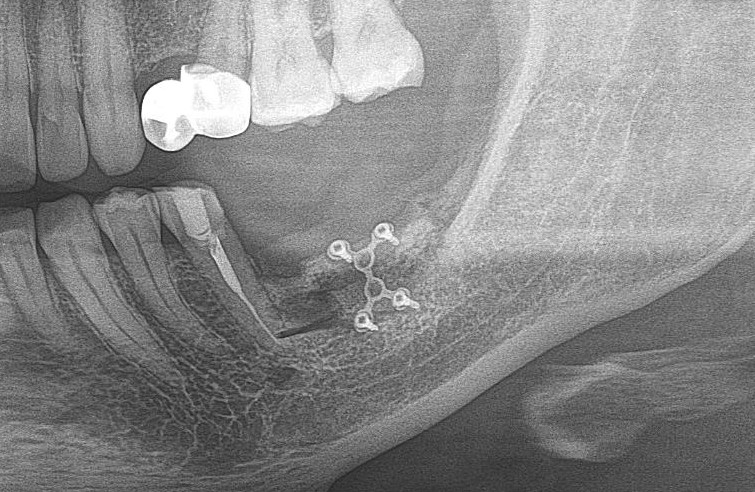

— контрольный снимок (раньше делали ОПТГ, сейчас — строго КЛКТ)

Для этого мы сделали КЛКТ:

И КЛКТ показала нам, что с имплантатами и окружающей костью всё зашибись. Через 12 лет после операции, отсутствия наблюдения, пофигизма в замене временных коронок! Нужны ли тебе еще какие-нибудь доводы в пользу долгосрочной эффективности метода?

Серия контрольных снимков на этапах: